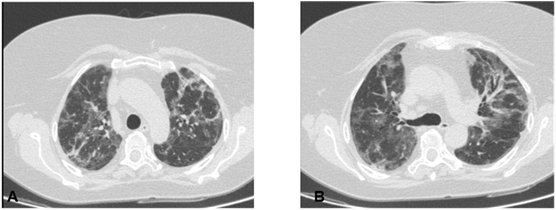

Computed axial tomography: The CO-RADS classification was taken into account, which is a standardized notification system for patients with suspected COVID-19 infection; this assigns a level of suspicion for the disease according to the findings found in the CT image. These range from very low, CO-RADS 1, to very high, CO-RADS 5, and CO-RADS 6, which corresponds to patients with typical findings and positive PCR4 (Figure 2).

Figure 2 CORADS 6.

Radiographic findings suggestive of COVID-19 are: focal opacities with a clear increase in density and with margins less defined than a nodule; focal or diffuse interstitial pattern and focal or diffuse alveolar-interstitial pattern.4

Tomographic findings in patients with COVID-19 have been classified as: typical, that is, there are multiple ground glass opacities of peripheral and basal distribution, vascular thickening, cobblestone pattern or disordered cobblestone (crazy paving); atypical findings, that is, para hilar, apical ground-glass opacities, and lymphadenopathy; and highly atypical findings, or in other words, cavitation, calcifications, nodular pattern, budding tree, masses, and pleural thickening.4